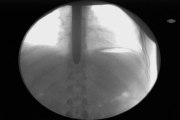

Sword Swallower Dan Meyer is a 40x World Champion Sword Swallower, multiple Ripley's Believe It or Not with 7 Guinness World Records and Finalist on America's Got Talent, known as the world's top sword swallower and leading expert in the field as president of the Sword Swallowers Association International, global TED speaker, and winner of the 2007 Ig Nobel Prize in Medicine at Harvard for sword swallowing medical research. <br /> <br />As a performer, Sword Swallower Dan Meyer is best known as the "Most Dangerous Act" that wowed the judges on America's Got Talent to Las Vegas and Hollywood, for his dangerous feats and extreme daredevil stunts such as swallowing swords underwater in a tank of SHARKS for Ripley's Believe It or Not, for swallowing a sword heated to 1500 degrees RED HOT for Stan Lee's Superhumans, swallowing 29 swords AT ONCE, and for PULLING a 3700 lb CAR by swallowed sword for Ripley's Believe It or Not Baltimore and on America's Got Talent Season 11, Italy's Got Talent and France's Got Talent. <br /> <br />http://CuttingEdgeInnertainment.com <br /> <br />Instagram: @Halfdan5 <br />http://instagram.com/Halfdan5